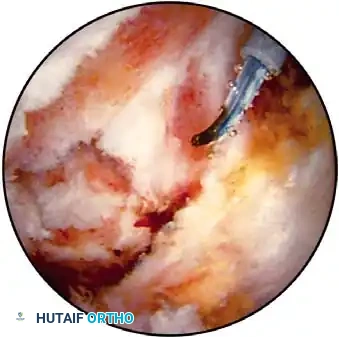

Electrocautery and Radiofrequency Ablation

In addition to hydrostatic pressure, active hemostasis is achieved using arthroscopic electrocautery or bipolar radiofrequency (RF) ablation devices. These wands are indispensable for coagulating bleeding vessels in the subacromial bursa, releasing the coracoacromial ligament, and meticulously preparing the footprint for rotator cuff repair without obscuring the visual field with hemorrhage.

Furthermore, the addition of epinephrine (typically 1 mg per 3 liters of irrigation fluid) induces local vasoconstriction, significantly reducing capillary oozing. When combined with controlled hypotensive anesthesia (maintaining mean arterial pressure between 70-80 mm Hg), the surgeon is afforded a pristine, bloodless field, allowing for the precise execution of complex knot-tying and tissue mobilization.